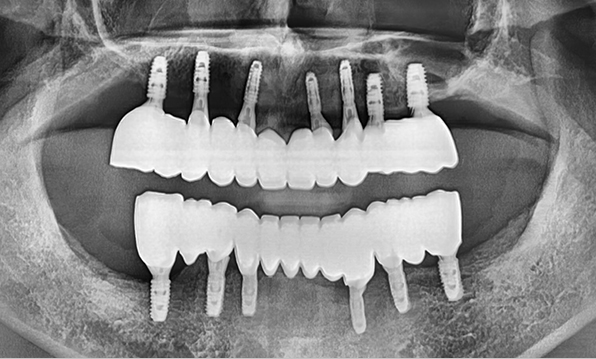

전체 임플란트

위 아래 치아가 정확하게 맞아야하는 고난이도 임플란트

임상 경험이 많은 숙련된 전문의의 섬세한 기술력이 중요합니다.

3D 디지털 진단을 통한 체계적인 계획

전체 임플란트는 위턱과 아래턱의 교합, 잇몸뼈의 상태 및

얼굴 변화 등 모든 것을 고려해 식립해야 합니다.

서울더자연치과는 3D 디지털 기술의 정밀 진단을 바탕으로

수술 계획을 세워 수술을 집도합니다.

치료기간 : 2021.04.12~2021.09.15